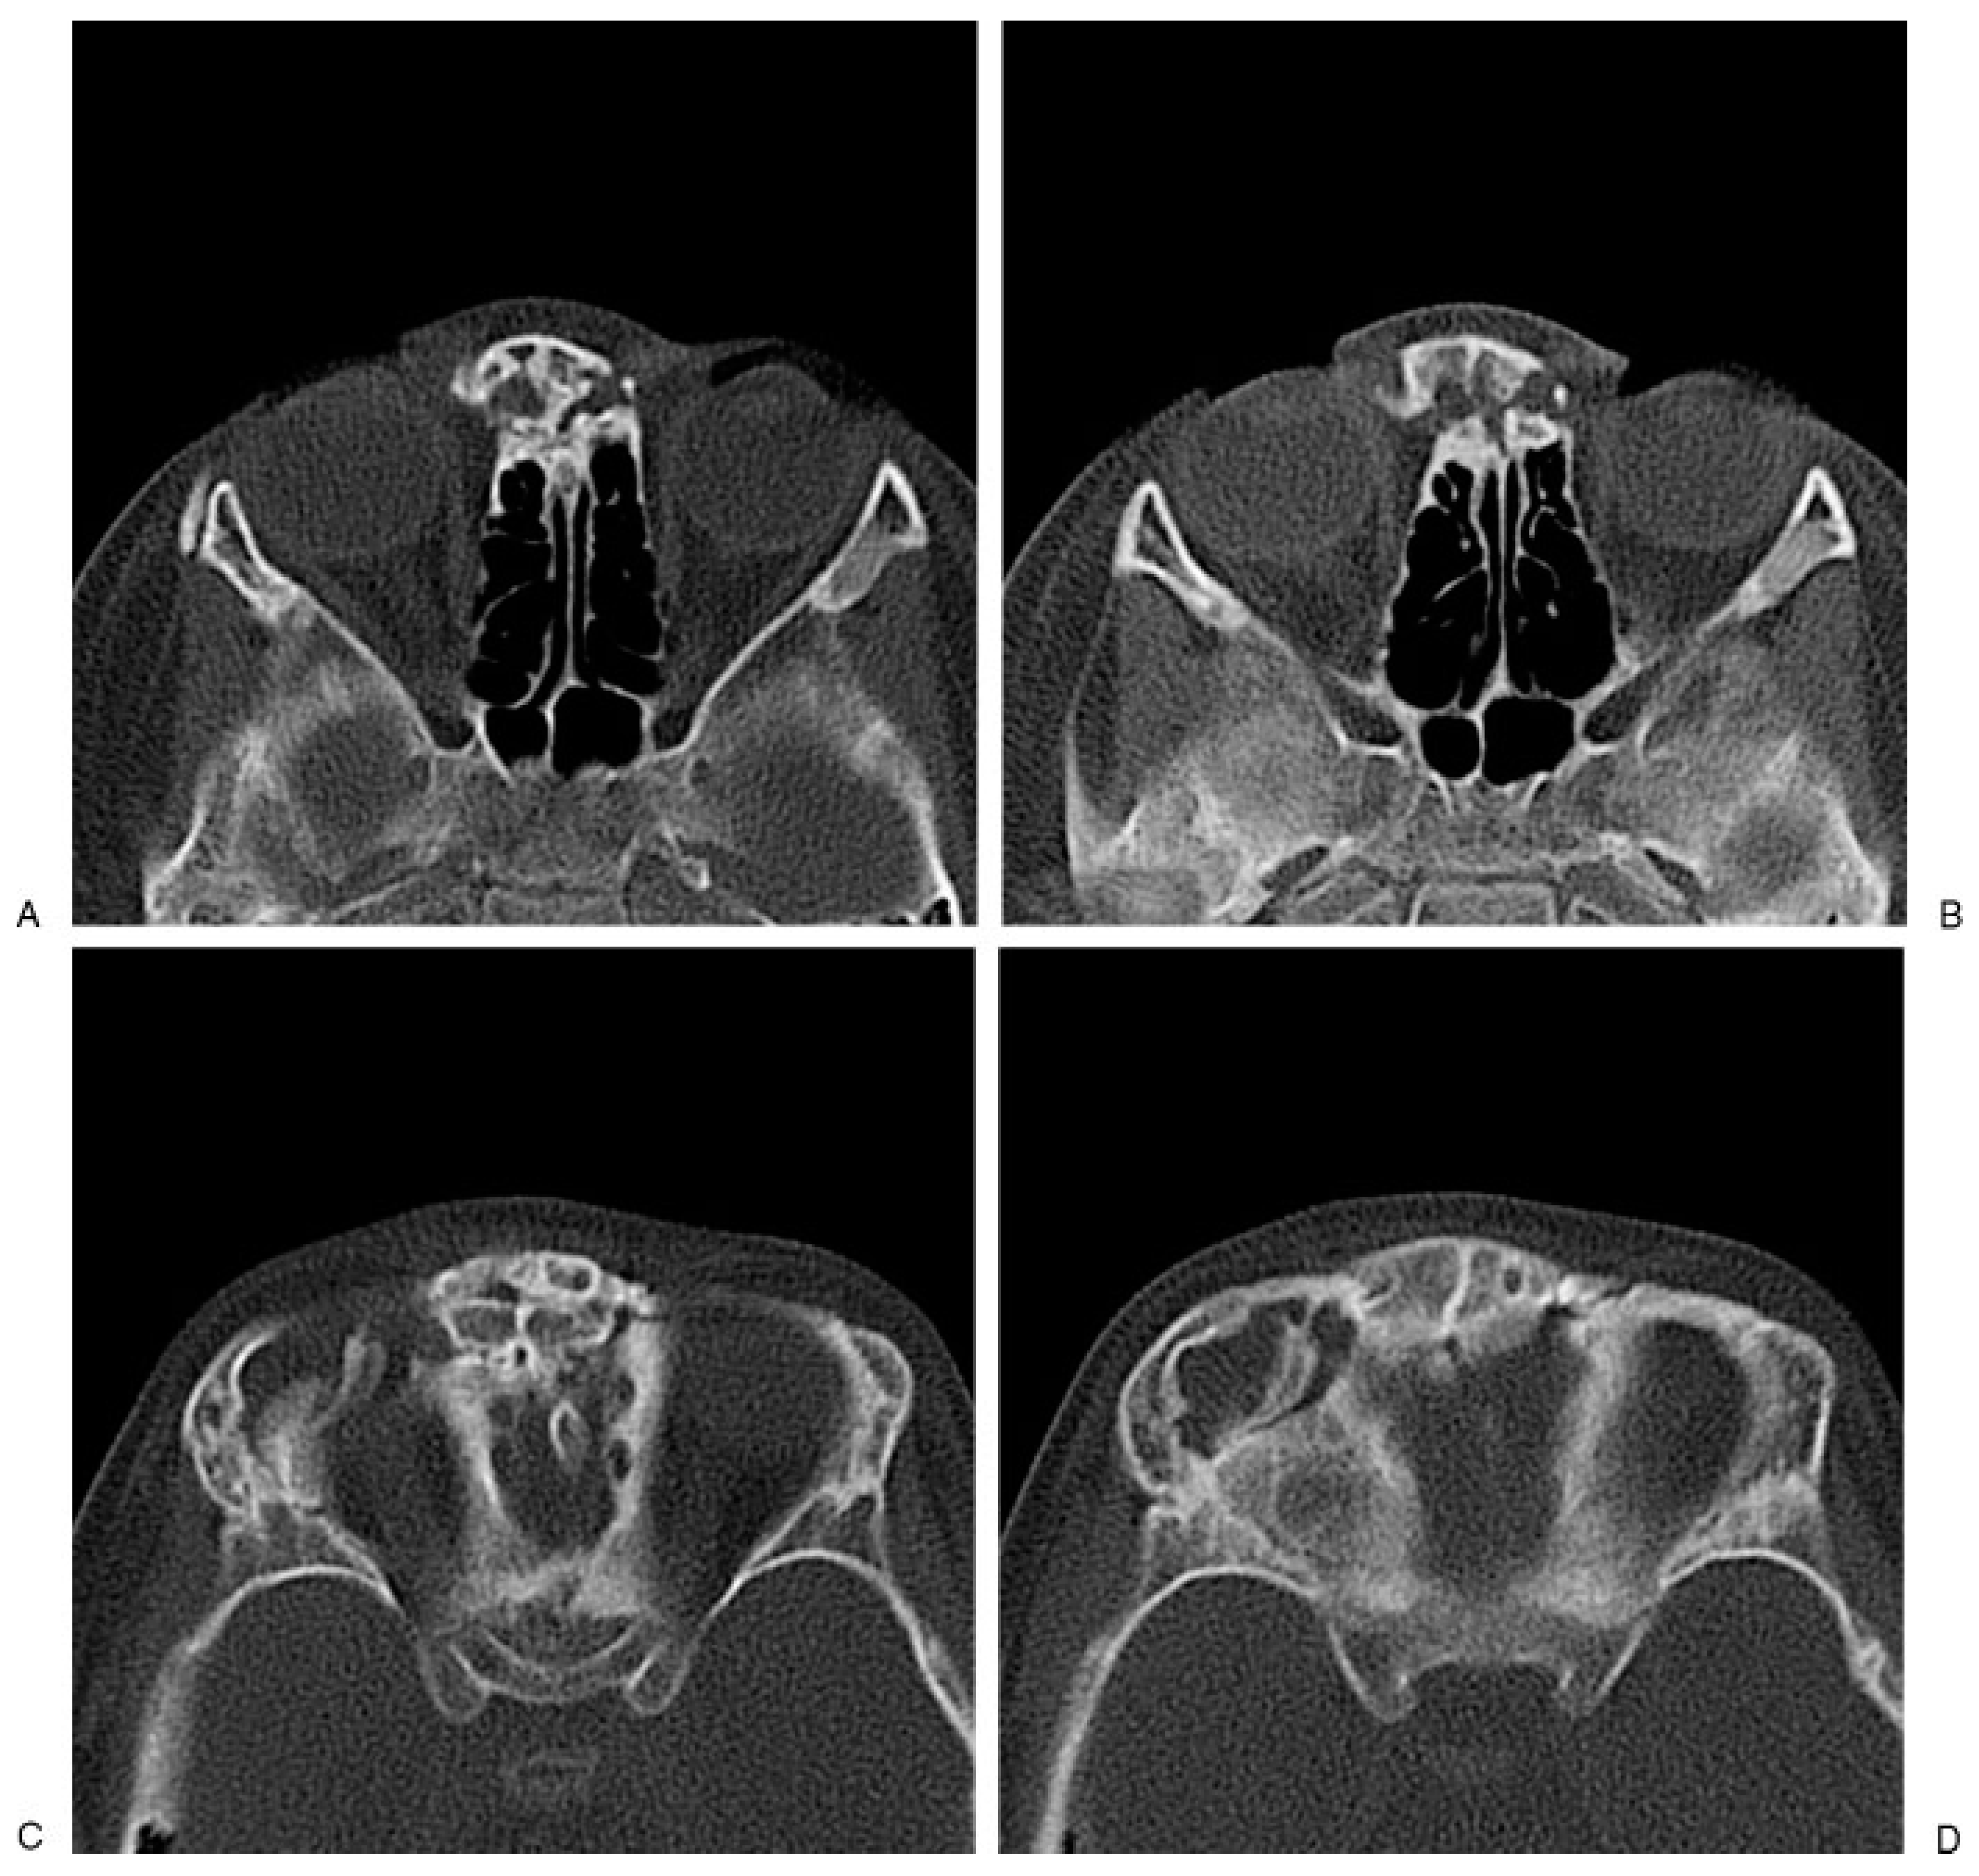

Following an injury to the upper facial area, clinical examination of the child is often difficult. Pediatric patients are frequently unable or unwilling to provide a history and the parents may or may not be present to provide additional detailed information. The children are often uncooperative and become easily frightened and apprehensive. In some cases, there may not be a history of trauma to the child, but one can see telltale signs of a significant previous injury on physical examination and CT scans (Figure 4 and Figure 5).

Figure 5. (AD) Computed tomography scans of the child in Figure 4 reveal untreated naso-orbital-ethmoidal fractures with displacement of the nasal pyramid and telescoping of the ethmoid sinus and fractures involving the orbital roofs.